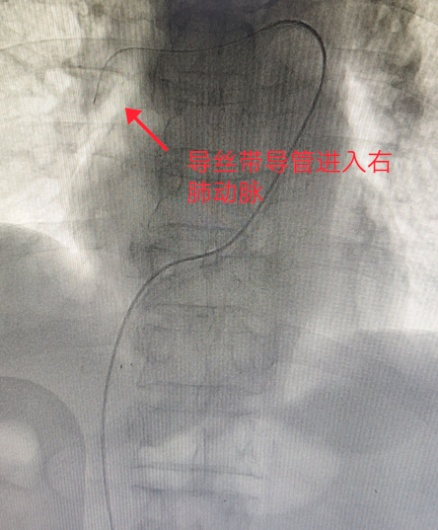

导丝带导管进入右肺动脉

考虑到老刘左下肢深静脉血栓持续形成且仍有脱落加重肺栓塞的风险,胡博士首先穿刺右侧股静脉放置下腔静脉滤器,拦截血栓。再经过穿刺的小口用导丝带导管进入肺动脉进行溶栓治疗。